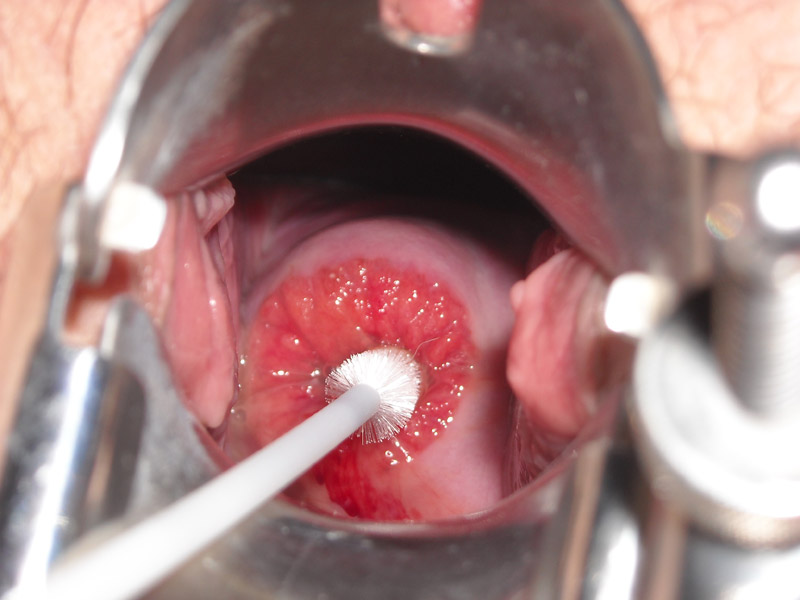

Эрозия шейки матки истинная является самым частым заболеванием у женщин в гинекологической практике. Это дефект многослойного плоского эпителия шейки матки. При осмотре визуализируется ярко-красное пятно с диаметром до 2 сантиментов с четкими краями. Эрозия располагается вокруг наружного зева матки. К образованию дефекта слизистой оболочки могут приводить многие факторы.

При осмотре эрозия представлена дефектом ярко-красного цвета с неровными краями. Излюбленным местом эрозии является задняя губа влагалища. Язвенный дефект кровоточит при прикосновении.

- Гинекологический осмотр в зеркалах

- Кольпоскопия – исследование при помощи кольпоскопа с тридцатикратным увеличением

- Мазок на цитологию для исключения воспалительного процесса и злокачественного образования (Папаниколау)

- Биопсия патологического участка ткани для гистологического исследования